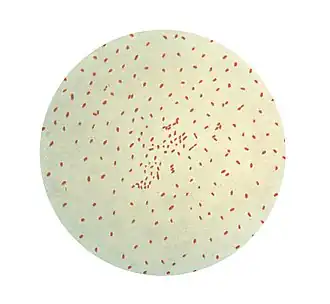

Bordetella pertussis, der Erreger des Keuchhustens, ist ein unbewegliches, aerobes, bekapseltes gramnegatives Stäbchenbakterium. Es produziert viele verschiedene Proteine, die teilweise als Toxine die Krankheitssymptome verursachen, teilweise dafür verantwortlich sind, dass die Erreger gut an den Schleimhäuten der Atemwege anhaften und sich dort vermehren können (Virulenzfaktoren). Eine Infektion mit Bordetella parapertussis führt nur in weniger als einem Fünftel der Fälle zum klinischen Bild des Keuchhustens. 40 % der Infektionen verlaufen stumm und weitere 40 % als einfache akute Bronchitis.[3]